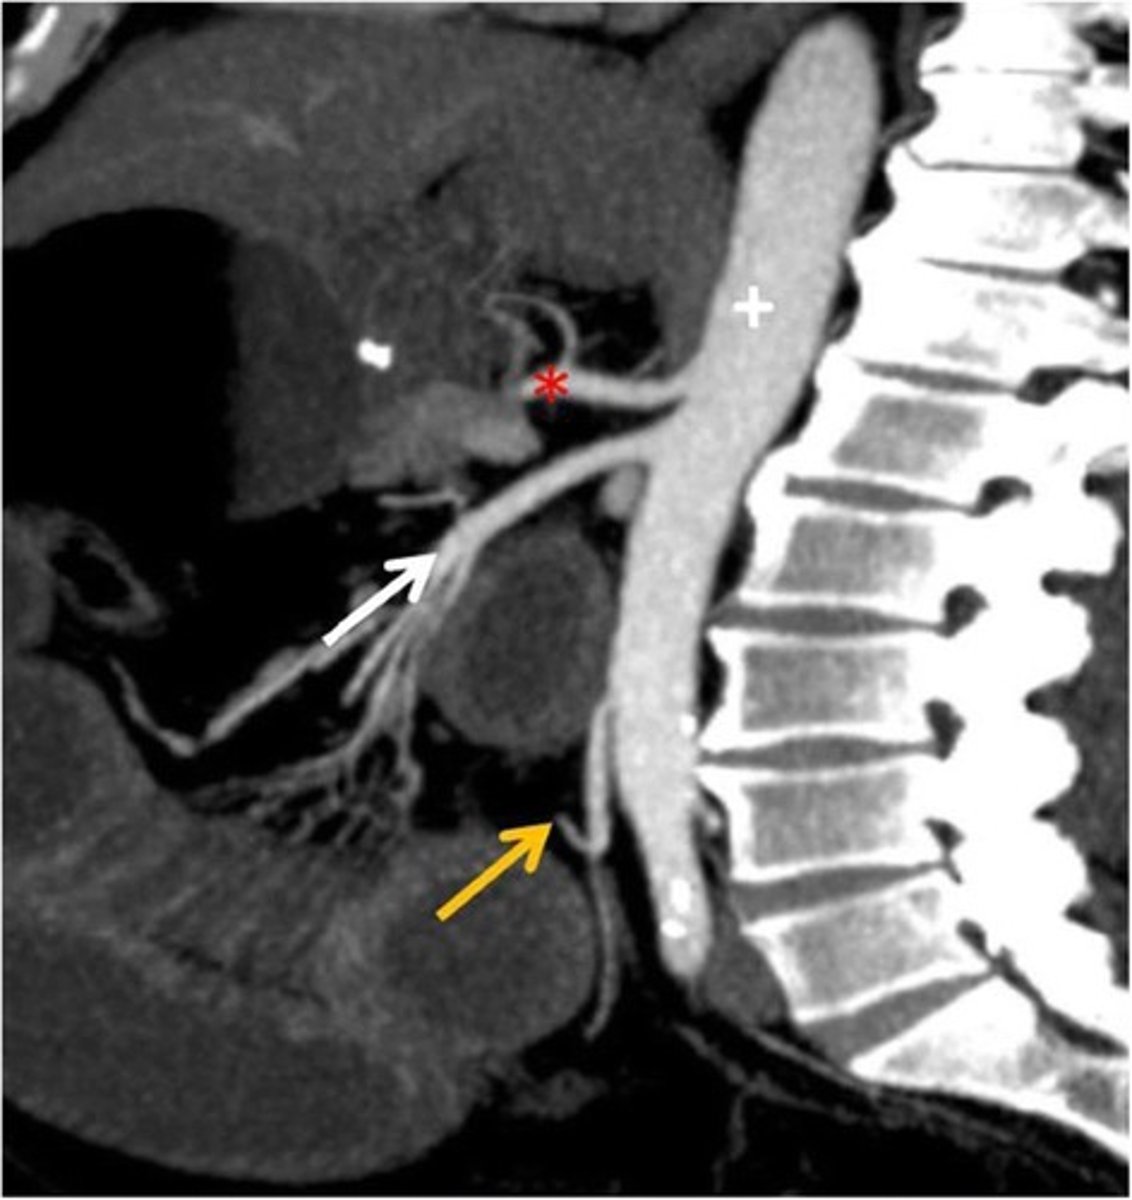

CT Sagittal

What type of image is this

Celiac trunk

What is the red star artery

superior mesenteric artery: midgut

What is the white arrow artery

Inferior mesenteric artery; hindgut

What is the yellow arrow artery